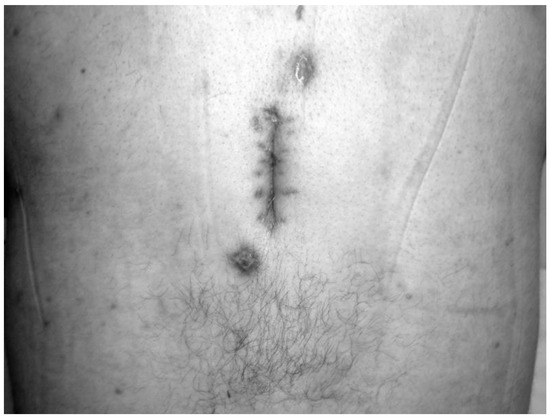

Figure 1. The appearance of the wound with purulent drainage in the operation site prior to HBO2 treatment.

Figure 2. Discharge from the wound site stopped and complete wound healing was achieved at the end of HBO2.

All patients who received HBO2 treatment (seven males, six females) had a prior history of spinal surgery. The primary diagnosis was spondylolisthesis in one patient, fracture in two patients, stenosis in three patients, and disc herniation in seven patients. The mean time between diagnosis and HBO2 treatment was 7.8 weeks. In patients referred after 2012, however, this time was 5.2 weeks. The primary symptom of all patients was pain. On admission, five patients (38%) were able to stand and walk without assistance, three patients (23%) were able to stand and walk with assistance, and five patients (38%) were unable to stand and walk because of severe pain. Conservative orthopedic treatment consisted of immobilization with rigid orthosis (hard cervical collar, thoracolumbar rigid brace, lumbosacral corset), which continued until complete healing of infection. There was also a discharging wound or sinus in the operation site in five patients. A daily wound dressing was applied in this group. In four of these five patients (80%), complete wound healing was achieved at the end of HBO2 therapy (Figure 1 and Figure 2).